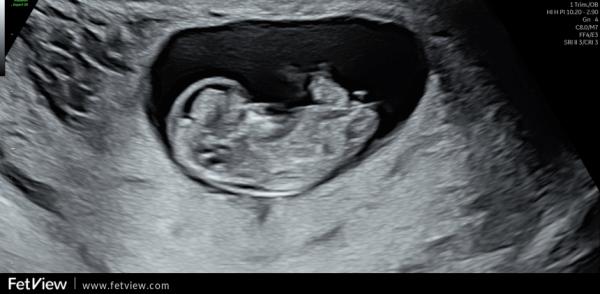

Huhu liebe Letti, ich gucke auch immer mal gerne in die anderen Gruppen rein 🤭 Deine Bilder muss ich wirklich sagen sind sehr schwierig. Würde aber einen Hauch mehr zum Jungen tendieren. Beim Mittleren ist über dem sticht noch ein kleiner kurzer Strich, den haben die Mädels nicht. Ebenso fehlt diese typische Mädchen gabelung vorne. Und bin mir nicht ganz sicher, ob der obere Strich bei (ich glaube bei dem letzten Bild war es) ein ganz kleines mini bisschen mehr nach oben geht. Ich kann es mir aber auch einbilden. Ich muss ehrlich sagen, dass ich die Nub Theorie unfassbar spannend ist und am liebsten den ganzen Tag so Bilder angucken könnte und neugierig bin, was es letztendlich dann ist 🤭

Oh, ich bin ja ganz bei dir. Finde das auch total spannend. Auch wenn das natürlich keine 100% Garantie gibt. Ich muss gestehen, dass ich mich danach ein wenig reingelesen habe und das Ganze trotzdem nicht 100% verstanden habe 🤔😃 Meine Bilder sind aber auch nicht so eindeutig, wie die, die man im Internet (meist) findet. Gerade beim letzten Bild hätte ich eher auf ein Mädchen getippt, weil das für mich so parallel aussah, wo ich eingekreist habe 🥰 Der weiße "Strich/Fleck" oberhalb von dem orangenen Kreis gehört zum Bein. 🤭 Einfach spannend 😍

Ich find es halt interessant, weil die Ärztin bei der Feindiagnostik auch damit anfing und das nochmal erklärt hatte. Schade, dass man den Nub nicht so genau erkennen kann. Oder man kann ihn sehen aber unser ungeschultes Auge bekommt es nicht gebacken 😂 Ich weiß was du meinst. Hab dein Bild frecher weise einfach mal "bemalt" um zu zeigen, was ich meine.

Genau. Das letzte Bild war es. Der untere Strich geht nach unten, der obere nach oben. Es sind nicht beide Parallel verlaufend nach unten.